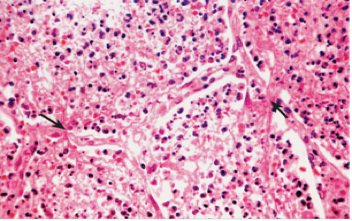

(2)红色肝变期 一般为发病后的3~4天进入此期。肉眼观,受累肺叶进一步肿大,质地变实,切面灰红色,较粗糙。胸膜表面可有纤维素性渗出物(图1-3)。镜下,肺泡壁毛细血管仍扩张充血,肺泡腔内充满含大量红细胞、一定量纤维素、少量嗜中性粒细胞和巨噬细胞的渗出物,纤维素可穿过肺泡间孔与相邻肺泡中的纤维素网相连,有利于肺泡巨噬细胞吞噬细菌,防止细菌进一步扩散(图1-4)。

图1-4 镜下观